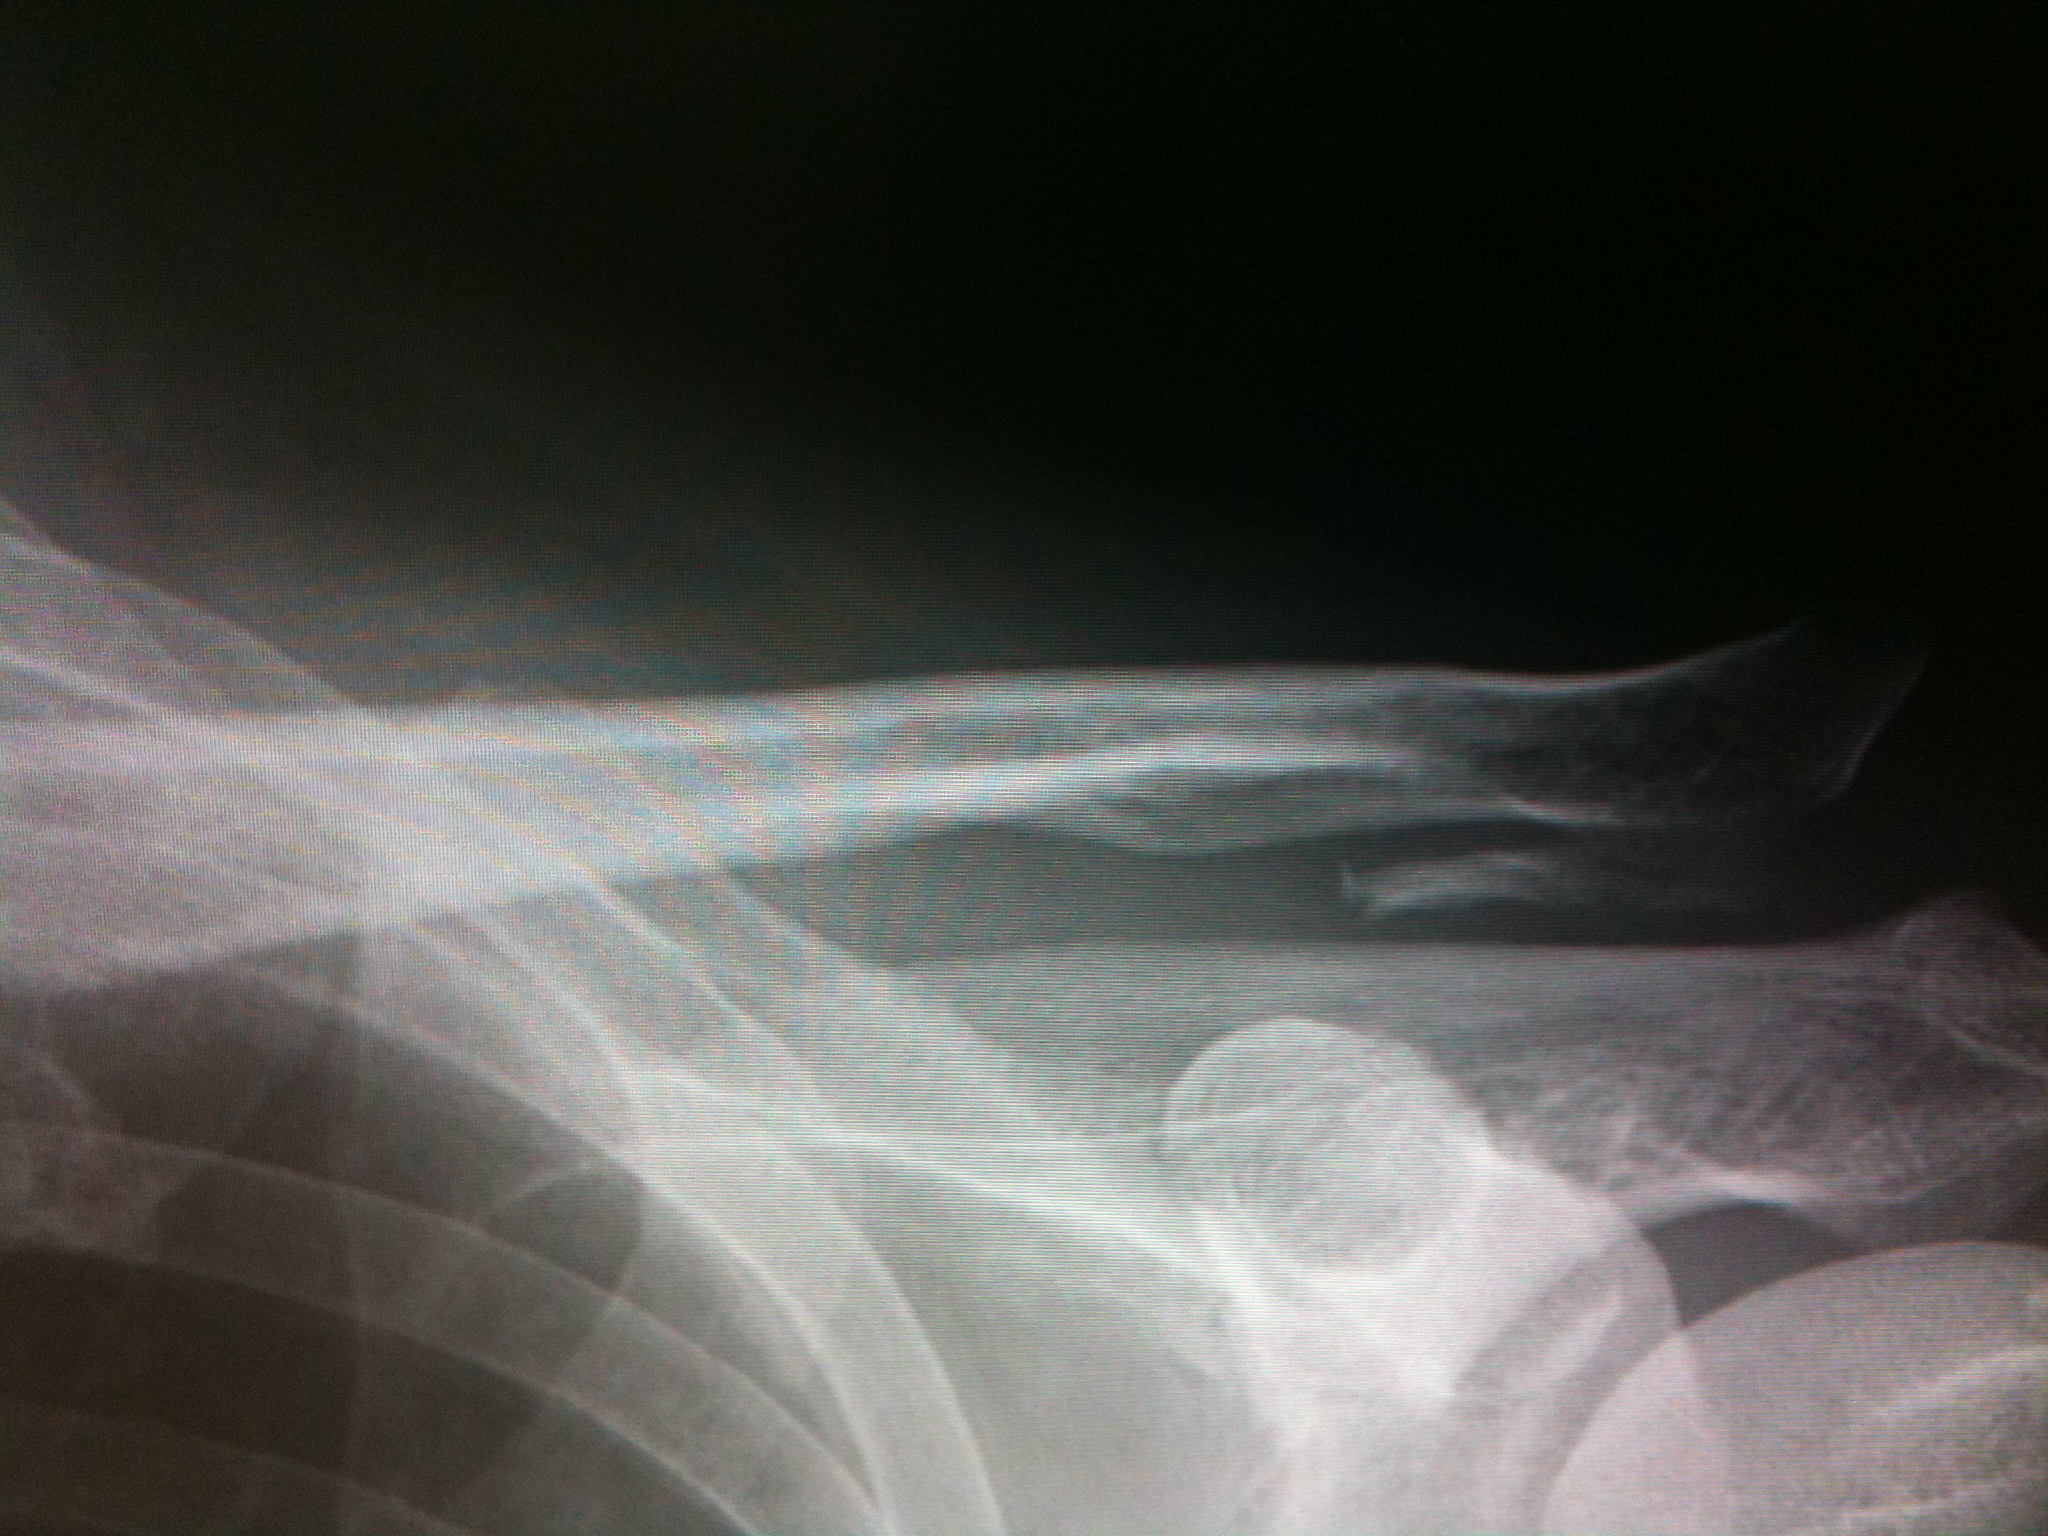

さて、そのレントゲンの結果ですが、

肩の骨の下に白い破片が見えます。

「こりゃけがしたときに骨膜をはがしていたか、剥離骨折していたかだね」

「それにしても肩から骨がずいぶん飛び出したね」